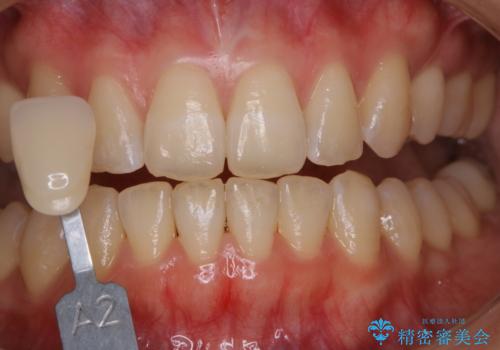

オフィスホワイトニング(エクセレントコース)

- オフィスホワイトニング希望で1日で白くしたいとのことでした。

オフィスホワイトニングのエクセレントコース(¥29700)を行いました。